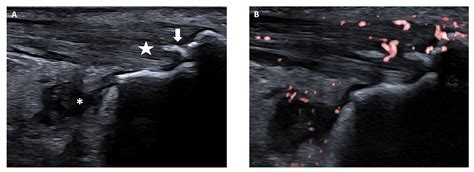

• Imaging studies: X-rays, MRI, or ultrasound to visualize the affected joints and entheses. MRI is particularly useful for detecting inflammation in the sacroiliac joints.